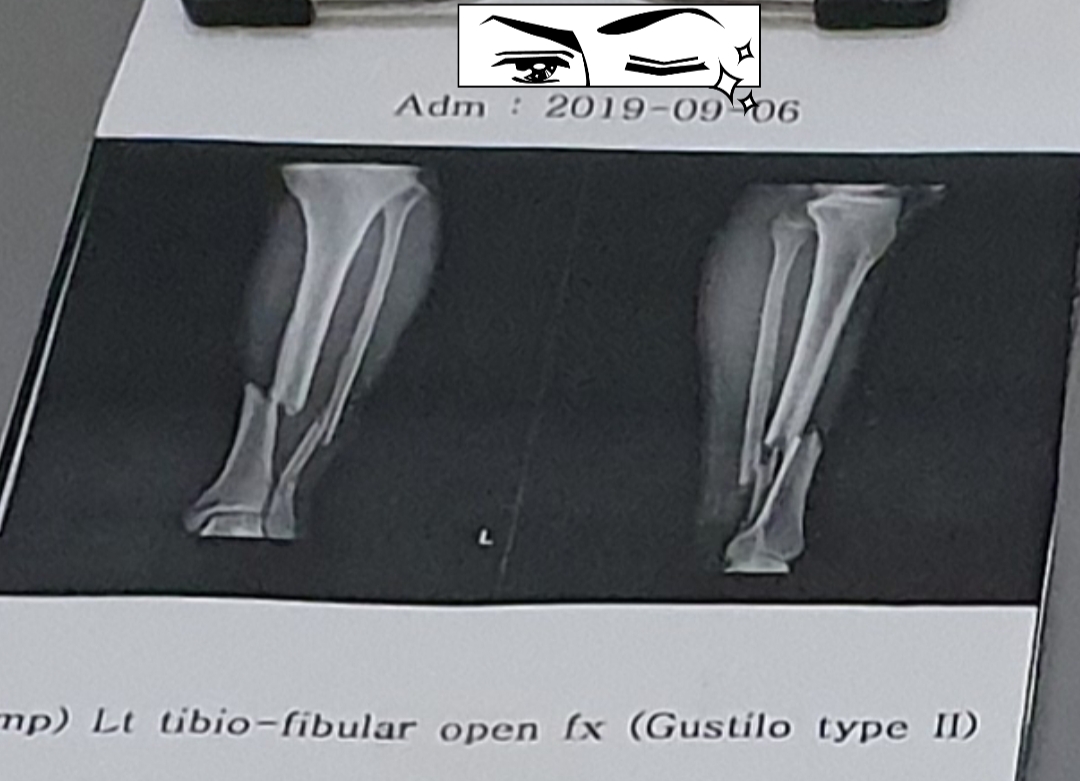

오늘 엑스레이 찍어보니 고정핀 하나가 부러짐...

저 티타늄 조각은 이제 나와 평생 함께 살 예정임 ㅋㅋ

오토바이 직진중 비보호 좌회전하던 SUV와 충돌 후 좌측 경골비골 개방골절, 후 7m정도 날라감

다리는 오토바이 사고로 부러진거고 클라이밍으로는 핀이 부러진거임 까먹고 본문에 안적어놨음

직업적 특성상... 사진을 유심히 보았는데 솔직히 말하면 두가지 정도가 의아합니다. 개방성 골절인데 외고정 수술을 하지 않고 바로 내고정 하신거는 뭐 집도의 의견이라 생각하고 그럴수 있다쳐도... 근 1년 팔로업 사진에서 골진액이 전혀 나오지 않거나 매우 소량만 나온것으로 보여서 매우 이상합니다. 옆에 fibular는 골진액이 충분히 나와서 어느정도 교정이 된것처럼 보이는데 tibia는 별 진전이 없는것으로 보아... 교정에 진전이 매우 더딘 상태입니다. 조금더 지켜보고 그대로이시면 부러진 부분만 절개해서 뼈이식을 하실 수도 있을거 같습니다. 사진만 보면 수술과정이나 앞으로 진행상태가 대략 짐작가는데 개별적으로 쪽지 주시면 성심껏 답변해드리겠습니다.

의사선생님도 그러더라 뼈붙는게 상당히 느리다고 아마 내년 겨울에나 철심빼지 않을까 싶음

나도 tibia & fibular open fracture였는데 tibia가 훨 오래 걸리긴 하더라. 이러다 안 붙는 거 아닌가 막 걱정하고 그랬음. 골진 왜 안 나와~~~ㅜㅜ 이러믄서